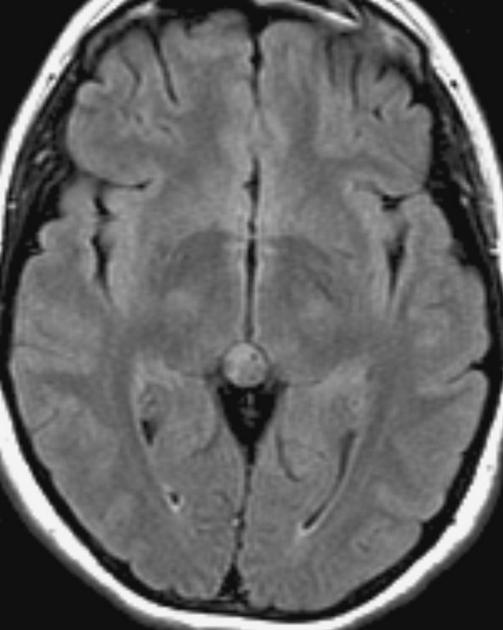

The general workup is MRI with T1/T2 images. Pineoblastomas are generally iso-enhancing on both T1 and T2, but T2 shows cystic components, at times becoming larger than the tumor itself. Surgical resection is treatment which also serves to provide tissue for diagnosis.

Pineocytoma T2 FLAIR